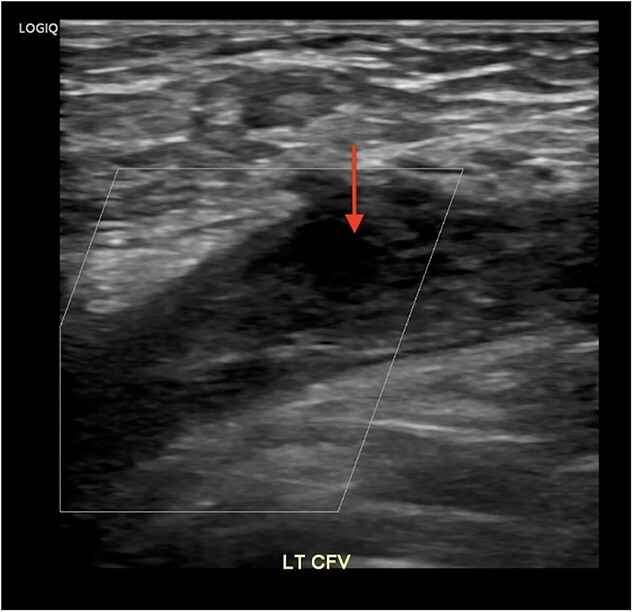

梅-瑟纳综合征(May-Thurner Syndrome, MTS)是由于左髂总静脉受压而导致深静脉血栓形成(DVT)。在深静脉血栓形成之前,MTS通常是无症状的。我们的病例是一名37岁的女性,她在最近的旅行和口服避孕药后出现左腿肿胀和疼痛。静脉双工超声证实深静脉血栓,CT血管造影排除肺栓塞。她接受了肝素抗凝治疗,并接受了机械取栓和支架置入术。她的症状在两天内得到改善,并在阿哌沙班和普拉维克斯的治疗下出院。该病例涉及一种独特的MTS患者表现,涉及一名患有不明原因左侧深静脉血栓的年轻女性,这种情况通常见于老年凝血障碍患者。

May-Thurner Syndrome (MTS) is caused by left common iliac vein compression, resulting in deep vein thrombosis (DVT). MTS is usually asymptomatic until DVT occurs. Our case features a 37-year-old woman who presented with swelling and pain in her left leg after recent travel and oral contraceptive use. Venous duplex ultrasound confirmed DVT and CT angiogram excluded pulmonary embolism. She received Heparin anticoagulation and underwent mechanical thrombectomy and stenting. Her symptoms improved within two days, and she was discharged on Apixaban and Plavix. This case involves a unique patient presentation of MTS, involving young woman with unexplained left-sided DVT, a scenario typically seen in older patients with clotting disorders.